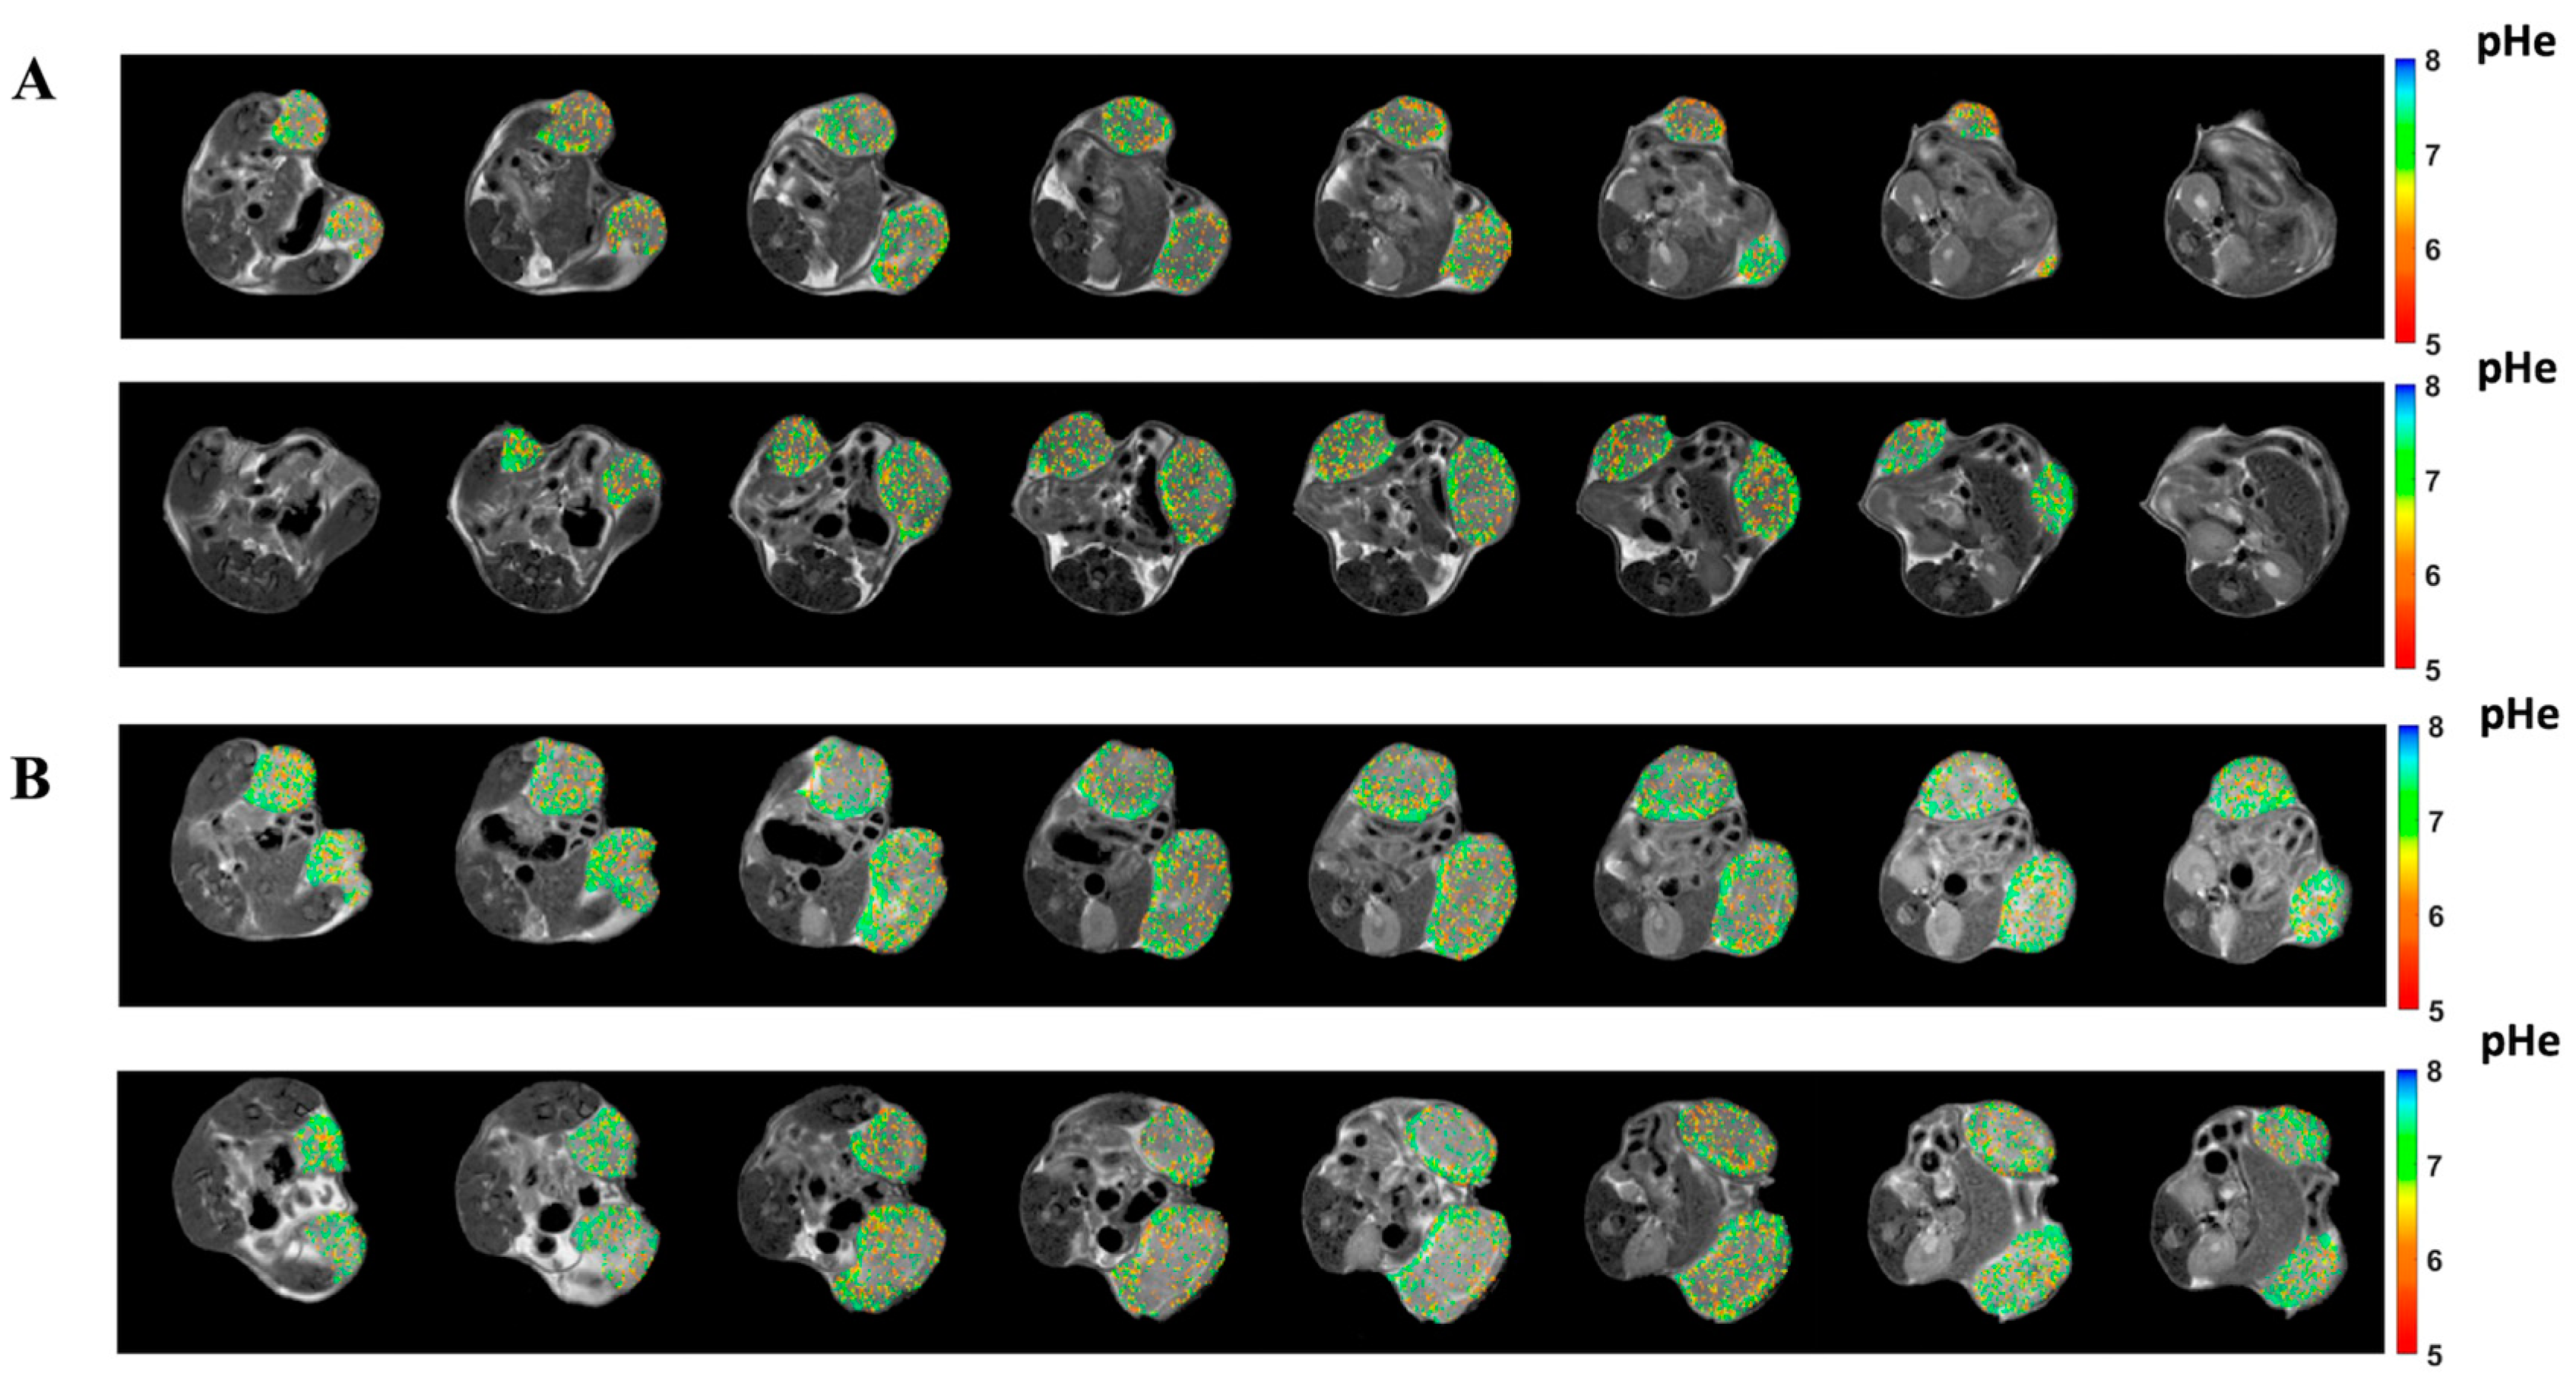

3.5. Lansoprazole Exhibits Increased Extracellular pH In Vivo Assessed through MRI-CEST pH Imaging

3.6. Amiloride Exhibits In Vivo Any Anti-Tumoral Effect and Is Ineffective in Altering Tumor pHe